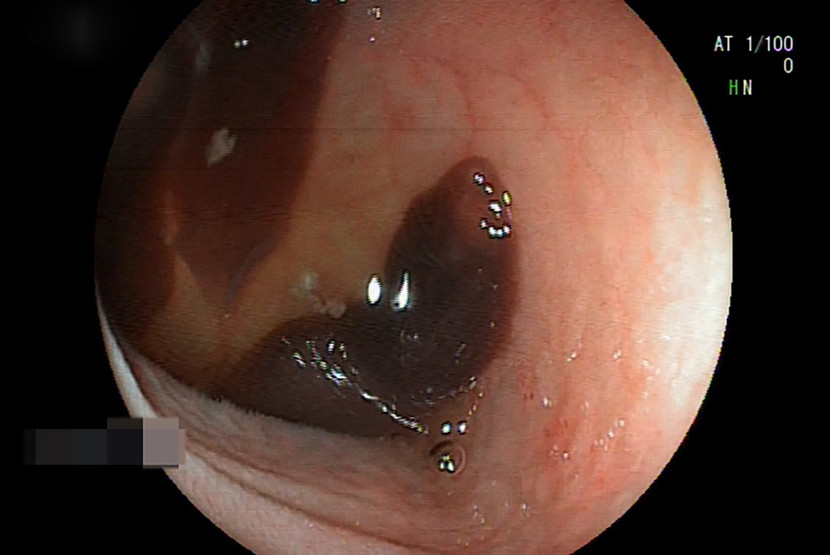

Ổ sán lá đang bám chặt vào thành ruột của bệnh nhân H. (ảnh bệnh viện cung cấp)

Kết quả nội soi cho thấy, ở hồi tràng (đoạn cuối ruột non) của chị H. có nhiều kí sinh trùng sán lá ruột lớn đang bám chặt vào thành ruột.

Bệnh nhân H. được bác sỹ chuyên khoa tiến hành gắp những con sán có kích thước 2 đến 3 cm ra khỏi ruột non.